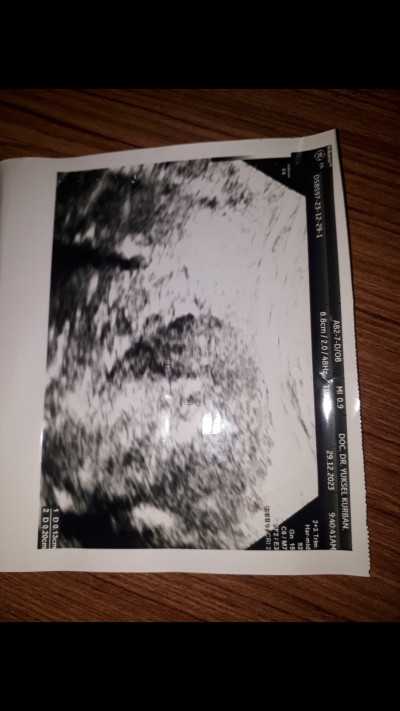

Kizlar agustos 5 inde 36 haftalik olu dogum yaptim. Suan hamileyim insallah saglikli olur. Ozelde Cuma gunu beta 35.18 cikti progesteron 6 cikti ama keseyi gördü. Kese milim çapında dedi ama degerlerin düşük dedi. Nekadarlik oldugunu bile soylemedi. Netlesmedi dedi. Dis gebelik yada kimyasal olabilir dedi. Carsambaya kadar kanamam olursa dusukle sonuclanirmis zaten ama olmazsa kontrol altinda bakacakmis. Sizce mümkünmü. Birde devletteki doktoruma gideceğim

image